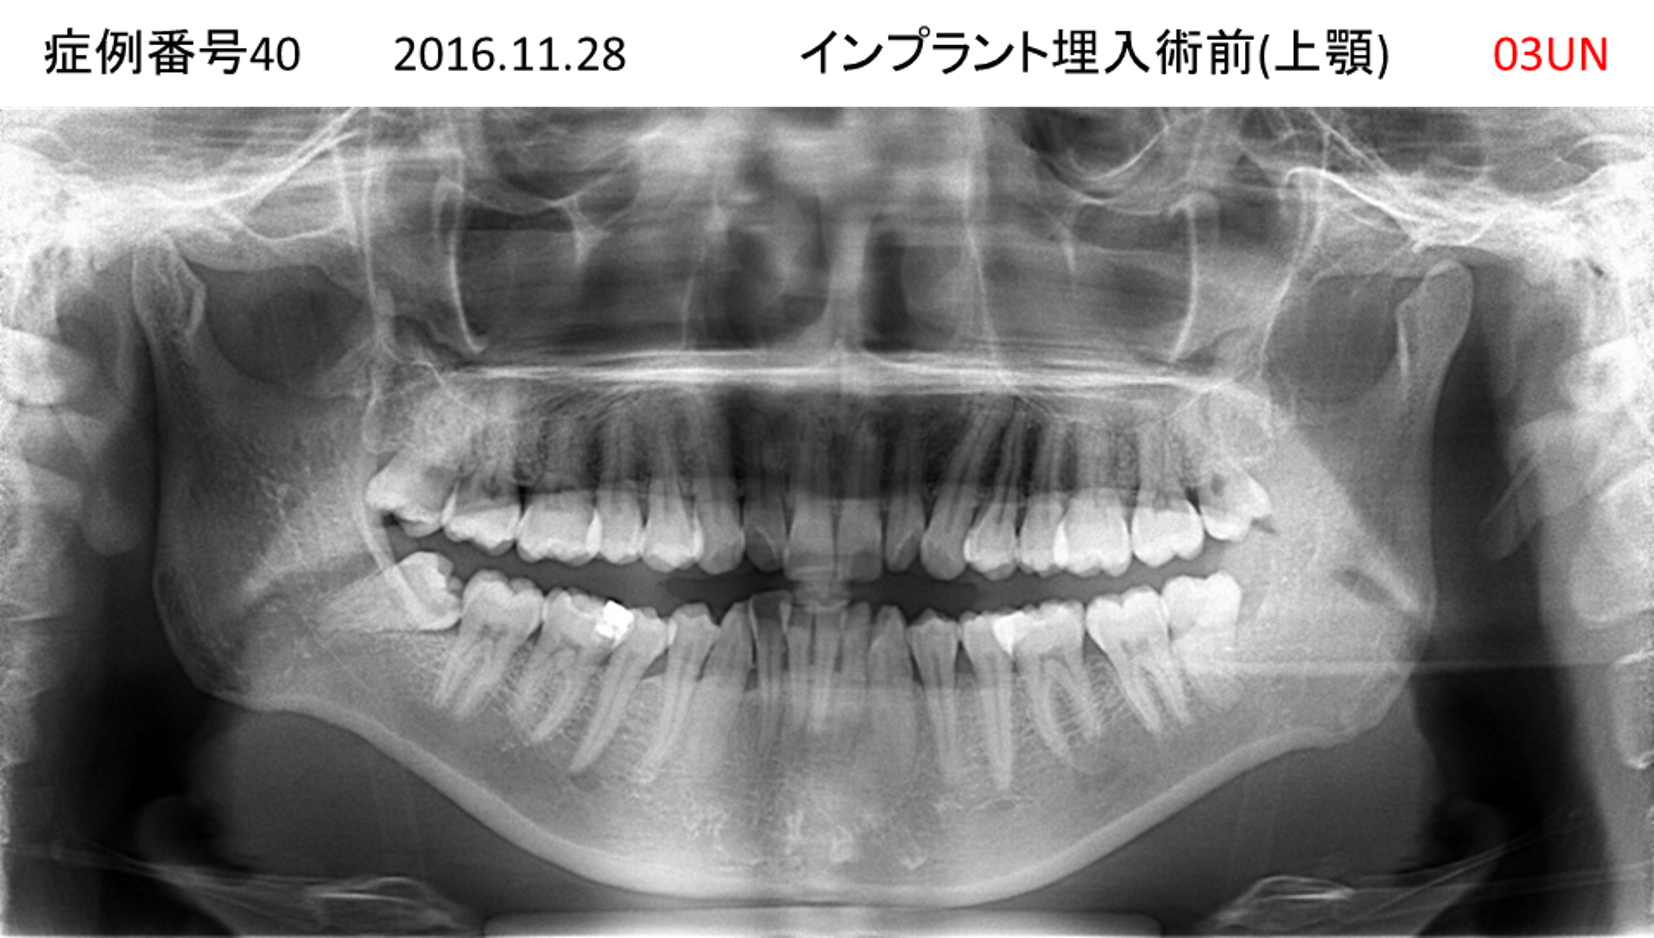

固いものが食べられない患者様のインプラント症例

| 治療名称 |

インプラント |

| 治療費用 |

405万円+税 |

| 治療期間 |

7か月 |

| 患者さんの症状(主訴) |

食事がうまくできない。固いものが食べられない。 |

| 治療内容 |

サイナスリフト、抜歯即時インプラント |

| 治療結果 |

食事に困らない、友人との外食が増えた、お肉が食べられる |

| 治療の注意点(リスク/副作用) |

インプラントが壊れたら再治療が必要 |